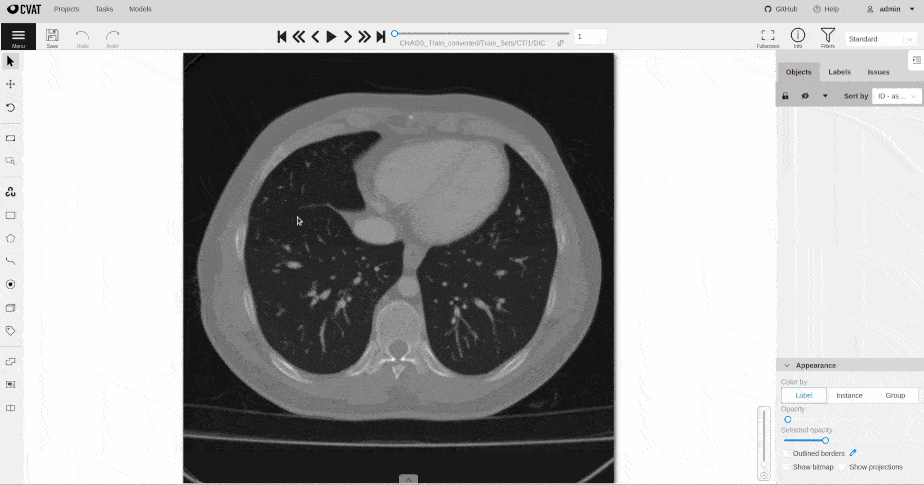

DICOM (Digital Imaging and Communications in Medicine) – это международный стандарт для хранения, передачи и визуализации медицинских изображений и связанной с ними информации. Представьте себе, что каждый производитель медицинского оборудования использовал бы свой собственный формат файлов. Это был бы хаос! DICOM позволяет различным устройствам и системам обмениваться данными без проблем совместимости. Это как универсальный язык, который понимают все.

Для нас, разработчиков, DICOM – это основа. Мы должны понимать структуру DICOM-файлов, уметь извлекать из них необходимую информацию (метаданные, пиксельные данные), и использовать её для анализа и обработки изображений. Без знания DICOM невозможно создать эффективную систему анализа медицинских изображений.

Примеры задач, которые мы решаем

Наши системы анализа медицинских изображений помогают врачам решать широкий спектр задач, например:

- Обнаружение опухолей. Мы разрабатываем алгоритмы, которые автоматически обнаруживают опухоли на КТ, МРТ и маммографических снимках.

- Сегментация органов и тканей. Мы создаем инструменты, которые позволяют врачам быстро и точно выделять органы и ткани на изображениях.